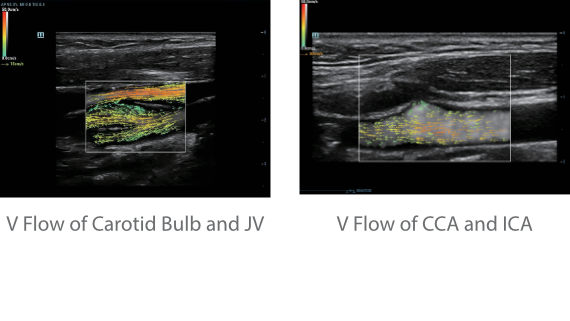

Обеспечивая качество изображения уровня премиум, Resona 7 также повышает клинические возможности исследования при помощи революционной системы V Flow, предназначенной для оценки гемодинамических показателей сосудов; обеспечивает интеллектуальное получение из 3D данных наиболее важных проекций для диагностики ЦНС плода. Сочетая в себе интуитивно понятное сенсорное управление с распознаванием жестов и все важные клинические характеристики, передовая система Resona 7 настоящая новая волна в сфере ультразвуковых инноваций.Благодаря перечисленным выше характеристикам, Resona 7 является доступным решением премиум-класса, которое удовлетворяет высоким требованиям клинической точности и эффективной диагностики в условиях современной перегруженной больничной среды.